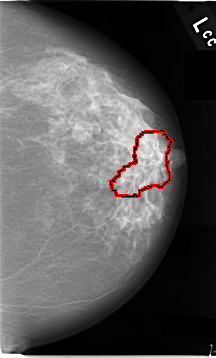

C_0006_1.LEFT_MLO

FILE: C_0006_1.RIGHT_MLO.OVERLAY

TOTAL_ABNORMALITIES 1

ABNORMALITY 1

LESION_TYPE MASS SHAPE IRREGULAR MARGINS SPICULATED

ASSESSMENT 5

SUBTLETY 5

PATHOLOGY MALIGNANT

TOTAL_OUTLINES 1

BOUNDARY